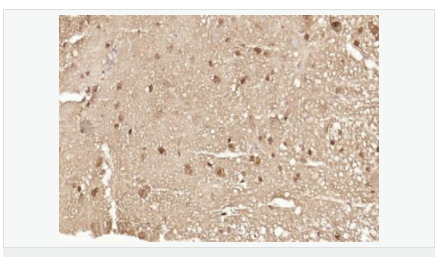

產(chǎn)品介紹The human ataxin-7 gene, also known as spinocerebellar ataxia 7 or SCA7, maps to chromosome 3p13-p12, has a 2,727-bp open reading frame, and encodes a 892 amino acid protein containing a nuclear localization signal and a polyglutamine tract (1,2). SCA7 is an autosomal dominant neurodegenerative disorder characterized by ataxia and selective neuronal cell loss caused by the expansion of a translated CAG repeat encoding a polyglutamine tract in ataxin-7, which is the SCA7 gene product (3,4). Ataxin-7 is expressed within neurons both affected and unaffected in SCA7 pathology with subcellular localization being variable depending upon the neuronal subtype (5). Polyglutamine expanded in ataxin-7 may carry out its pathogenic effects in the nucleus by altering the matrix-associated nuclear structure and/or by disrupting nucleolar function (6).

Ataxin 7 is a protein of unknown function. It may be the human orthologue of the yeast SAGA SGF73 subunit and a subunit of the human TFTC-like transcriptional complexes. Spinocerebellar ataxia 7 (one of a group of hereditary neurodegenrative diseases) is caused by an expanded trinucleotide repeat in the gene encoding ataxin 7. Ataxin 7 is typically located in the cytoplasm and on the nuclear membrane of normal brain neurons. In cells where there is a mutation of the SCA7 gene, ataxin 7 accumulates in intranuclear inclusions and can result in cell death.

Isoform a and isoform b are expressed in CNS, but isoform a is expressed predominantly in the peripherical tissues. Isoform b is also highly expressed in the frontal lobe, skeletal muscle and spinal cord and is expressed at a lower level in the lung, lymphoblast and intestine.